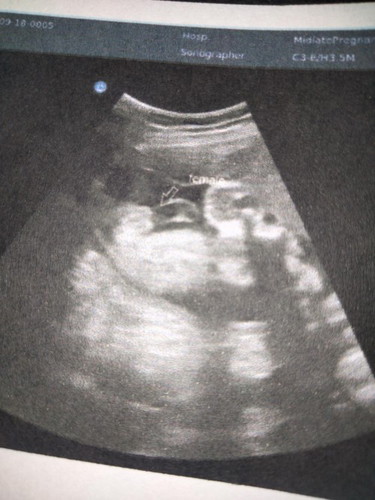

ภาพอัลตร้าชาวด์

ภาพอัลตร้าซาวด์ แม่ๆช่วยดูให้หน่อย หญิงหรือชาย

แม่ดูในฟิล์มที่ซาวด์ ใกล้ๆลูกศร ดูไม่ชัด ว่า femeleผญ. หรือ male ผช.

ข้างๆลูกศร เขียนว่า female ผู้หญิงค่ะ

เหมือนมี จู๋ เลยค่ะ